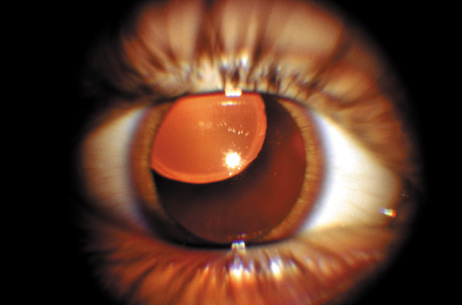

The dense bilateral lens opacities may present as a biconvex-shaped cataract or as posterior, polar, nuclear, or total cataract. The discoid lens shape may result from loss of lens material due to a posterior lens capsule defect4 or defective lens fiber formation and subsequent degeneration.5 The cataracts are present at birth, and glaucoma may be present congenitally or develop within the first 3 years of life. Other ocular findings may include corneal opacity, mitotic pupil, enophthalmos, and hypotonia.6 The cognitive impairment presents with a discrete behavioral phenotype that includes temper tantrums, irritability, complex repetitive behaviors, and unusual mannerisms. Severe renal Fanconi's syndrome may lead to progressive renal impairment. Most boys will develop a distinctive facies and habitus, and attain a height of less than 5 feet because of developmental retardation. Female carriers manifest characteristic but usually asymptomatic lenticular opacities that will correctly identify carrier status with 100% sensitivity in postpubertal females. These opacities are typically small, irregularly shaped, off-white or gray in color, nonrefractile in appearance, and distributed around the lens equator, more anteriorly than posteriorly (Figs. 1 and 2). Most importantly, and distinctively, these opacities are clustered in radial bands or wedges in the peripheral cortex of the lens and are visible by retroillumination. Typically, the opacities are moderately dense for one or two clock-hours, are then less numerous or even absent for another clock-hour or two, and so on. These opacities must be differentiated from the polychromatic, iridescent “crystals” found in Steinert's myotonic dystrophy (DM), gray-white random opacities in carriers of X-linked adrenoleukodystrophy, sutural opacities in Nance-Horan's (NH) syndrome, snowflake granules beneath the anterior and posterior capsule in diabetes mellitus, highly uniform white dots of hypoparathyroidism, and equatorial opacities in cataracta coronaria or ceruleana. Some females also manifest a dense white, central, posterior cortical cataract in the precapsular area. Although the posterior central cataract is apparently congenital, the equatorial and anterior cortical punctate opacities are uncommon in prepubertal female Lowe's syndrome carriers.7 Carrier status may also be confirmed by DNA diagnosis.

Fig. 1. OCRL. Female carrier with typical small, irregularly shaped, off-white or gray, nonrefractile opacities in the anterior lens cortex, slit-lamp view. (Courtesy of Dr. R.A. Lewis, Baylor College, Houston, Texas.)